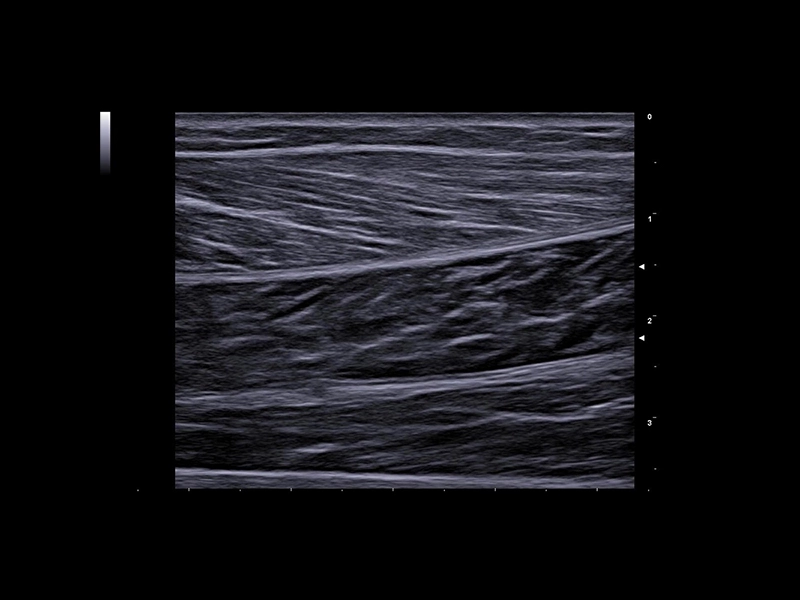

MyLab™X1 Go - Tendon

MyLab™X1 Go - Tendon